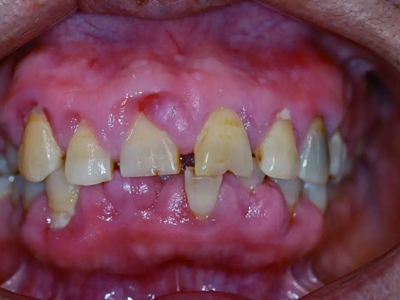

牙龈退缩牙根暴露出现黑斑图

牙龈退缩患者的上排多颗牙齿处的牙龈出现回缩,从而导致牙根外露,外露的牙根上存在黑色的牙菌斑、牙结石,伴有口臭、牙根面敏感等症状。